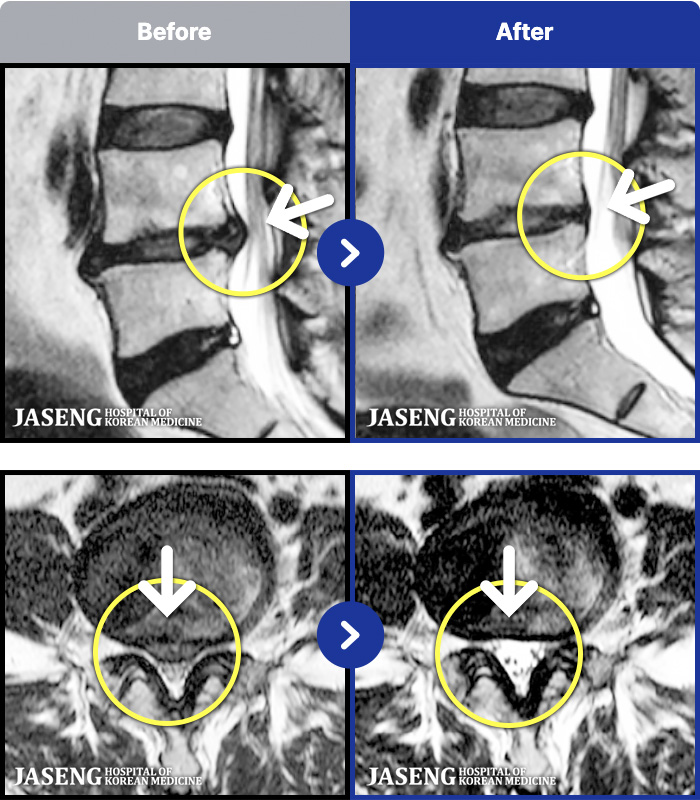

[] 23.11.11~25.06.04

ȯںп Ǹ ǿ ԿǾ, ο ġ ۿ Ƿ ġḦ Ͻñ ٶϴ.